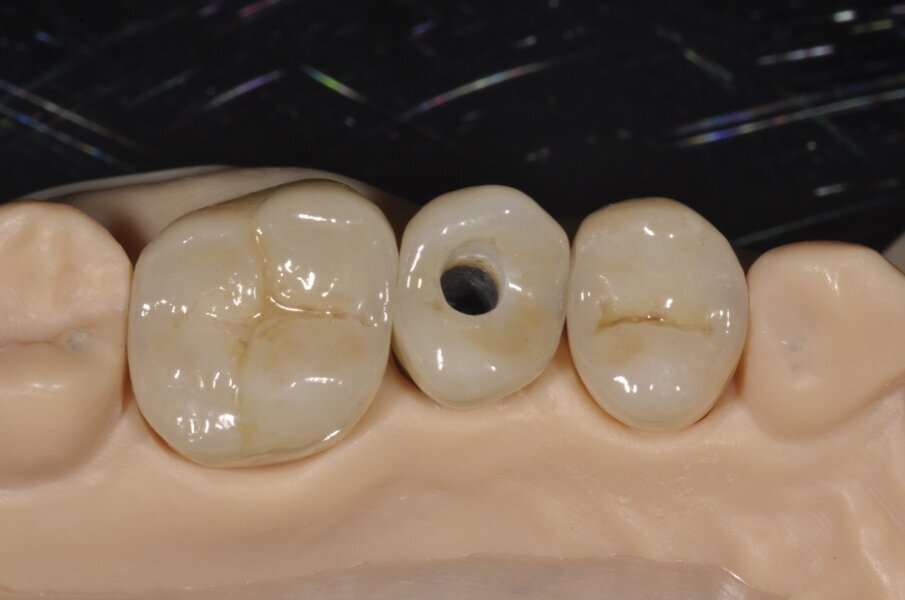

L’odontotecnico riceverà il file dell’intera impronta rilevata con l’IOS o direttamente, se collegato alla sistematica in questione o previo un formato STL che potrà essere gestito da qualsiasi sistema in uso CAD/CAM. La modellazione delle corone su denti naturali e su impianti potrà essere effettuata direttamente col software collegato andando a rilevare la linea di finitura della preparazione naturale e valutando o la realizzazione del moncone personalizzato, nel caso di una corona su impianto cementata o direttamente una corona avvitata (Fig. 11). In tal caso le ipotesi potranno essere quelle di realizzare una struttura unica che dalla connessione implantare modellerà la corona emergente o l’utilizzo di un moncone standard che verrà cementato alla corona che a sua volta potrà essere avvitata nella sua globalità all’impianto.

La conformazione degli elementi naturali e dell’emergenza implantare potrà essere modellata direttamente dal tunnel mucoso rilevato durante l’impronta, potendo calibrare un certo grado di pressione da esercitare nel tragitto transmucoso stesso (Fig. 12). La realizzazione del modello è un evento successivo che l’odontotecnico può realizzare direttamente o delegare a centri di fresaggio per la costruzione in un tempo successivo e per la gestione della ceramizzazione degli elementi realizzati. La casa costruttrice dell’impianto dovrà fornire l’analogo che avrà stessa connessione ma la forma esterna sarà diversa dovendosi incastonare nel tunnel realizzato dal fresatore nel modello in resina o nel materiale di realizzo. La precisione di questi modelli nella valutazione del dente naturale non è sovrapponibile a quella realizzato in gesso ma è anche una funzione diversa in cui tale margine non inficia il risultato finale di precisione e di realizzo delle corone. Le strutture potranno essere provate in fase interlocutoria per valutare l’adeguatezza e per rilevare l’esatta centrica, sarà così rinviata alla fase successiva di lavorazione per la finalizzazione del manufatto (Fig. 13). La scelta tra un manufatto avvitato ed uno cementato è puramente delegata al clinico secondo le abitudini e le necessità, oltre alla tipologia di protesi confezionata e dei materiali impiegati6. Laddove si delinea la possibilità di eseguire una costruzione protesica in cui l’estetica e la funzione non siano intaccati, l’attuale orientamento spinge favorevolmente il clinico ad una soluzione avvitata, evitando le infiltrazioni di cemento che potrebbero intaccare il mantenimento della riabilitazione implanto supportata.

Fig. 13 - Il restauro al termine della lavorazione e dopo le varie prove interlocutorie consegnate sul modello ottenuto per fresaggio.